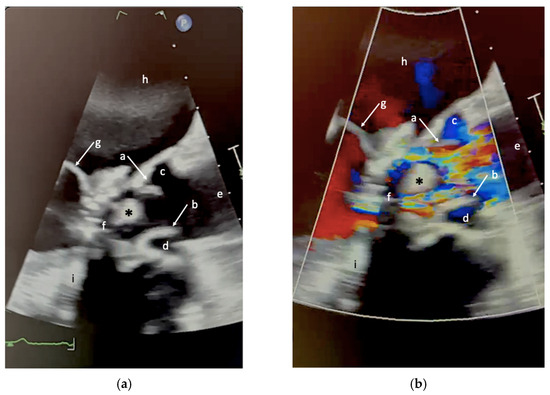

Unusual Native Valve Remnant in the Left Ventricular Outflow Tract After Valve-in-Ring Transcatheter Mitral Valve Replacement

by Sergio Enea Masnaghetti, Fabiana Isabella Gambarin, Stefano Maffè, Marco Gnemmi, Michela Conti, Andrea Audo and Massimo Pistono

J. Clin. Med. 2026, 15(5), 1732; https://doi.org/10.3390/jcm15051732 - 25 Feb 2026

Background and clinical significance. Valve-in-ring (ViR) transcatheter mitral valve replacement (TMVR) is an established therapeutic option for patients with failed surgical mitral valve repair at high surgical risk. Left ventricular outflow tract (LVOT) obstruction and prosthesis-related complications are well described, but other [...] Read more.

Background and clinical significance. Valve-in-ring (ViR) transcatheter mitral valve replacement (TMVR) is an established therapeutic option for patients with failed surgical mitral valve repair at high surgical risk. Left ventricular outflow tract (LVOT) obstruction and prosthesis-related complications are well described, but other postprocedural findings remain poorly characterized. Case presentation. We report a challenging case of a persistent LVOT mass following ViR TMVR. A 78-year-old man underwent transapical ViR TMVR with a Sapien 3 valve for mitral stenosis. Early post-procedural echocardiography showed normal prosthetic function and no LVOT obstruction. During inpatient cardiac rehabilitation, transthoracic echocardiography revealed a mobile mass in the LVOT. The patient did not show any clinical, microbiological, or laboratory evidence of infection. Blood cultures were negative, and the mass showed no changes despite anticoagulation. Two- and three-dimensional transesophageal echocardiography demonstrated a mobile structure attached to the mitral prosthetic ring by a thin peduncle. After a comprehensive multimodality assessment, thrombus and infective endocarditis were considered unlikely. The mass was ultimately interpreted as a displaced remnant of the native anterior mitral leaflet. Given the prohibitive surgical risk and absence of complications, conservative management with echocardiographic follow-up was adopted. Conclusions. This case study emphasizes the role of advanced echocardiography and multimodality analysis in avoiding misdiagnosis and inappropriate therapeutic interventions. Full article

(This article belongs to the Special Issue New Insights into Transcatheter Mitral Valve Therapy)

Show Figures

Figure 1